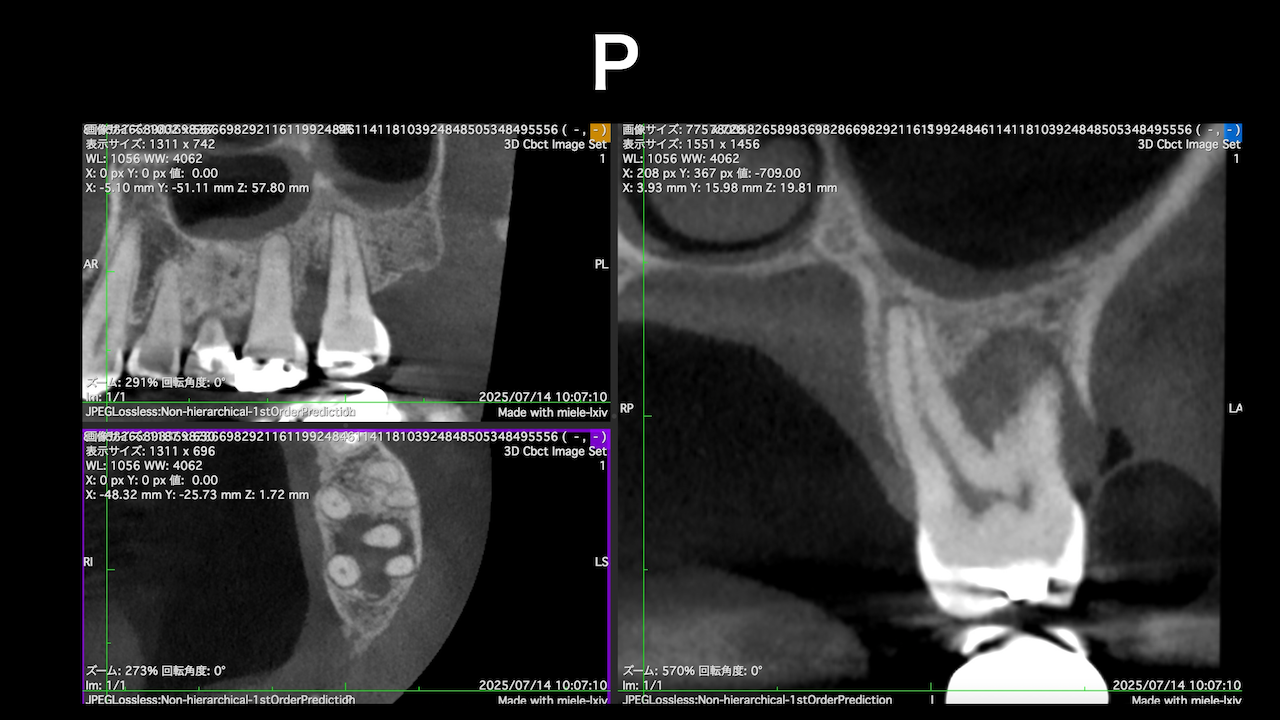

#7がCold testに無反応である。

故に、#7,8の非外科的根管治療を行うことになった。

CBCTでは2本とも口蓋側の皮質骨が消失している。

ここから4ヶ月が経過すると…

臨床症状も皮質骨も大きく治癒している。